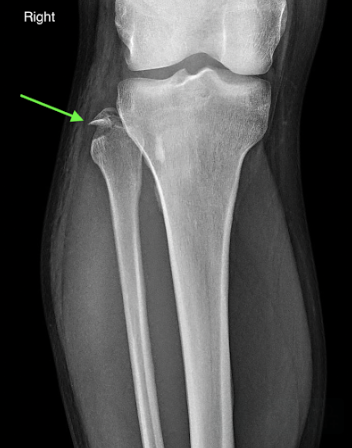

A 21-year-old female presents to the emergency room after falling from dancing on a table and injuring her right ankle. She is in severe pain and unable to bear weight comfortably with swelling and tenderness along the lateral malleolus. X-rays are taken and shown above.